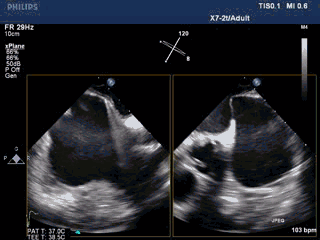

手术过程—PASS原则,残余分流

Seal:封堵器贴壁良好,各切面无残余分流。

手术过程—封堵器最终释放

PASS原则全部通过,封堵器释放,效果满意,手术结束。